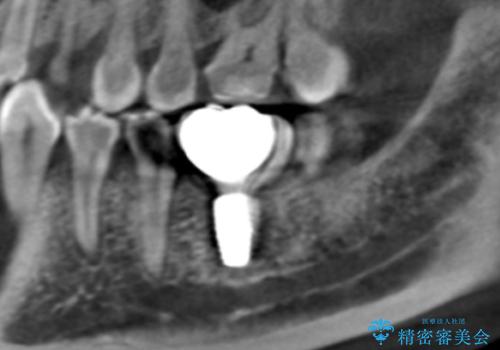

その過程で左下の6番目の歯は治療が必要な状態であることが分かり、被せ物を外して内部を確認してみると根が破折してしまっていることが判明しました。

歯が深い位置で破折している場合は基本的には抜歯が選択されます。

様々な治療プランを患者さんと相談させて頂き、最終的にインプラントで噛み合わせを回復させていくこととなり、まず悪くなっている歯を抜歯することから開始しました。